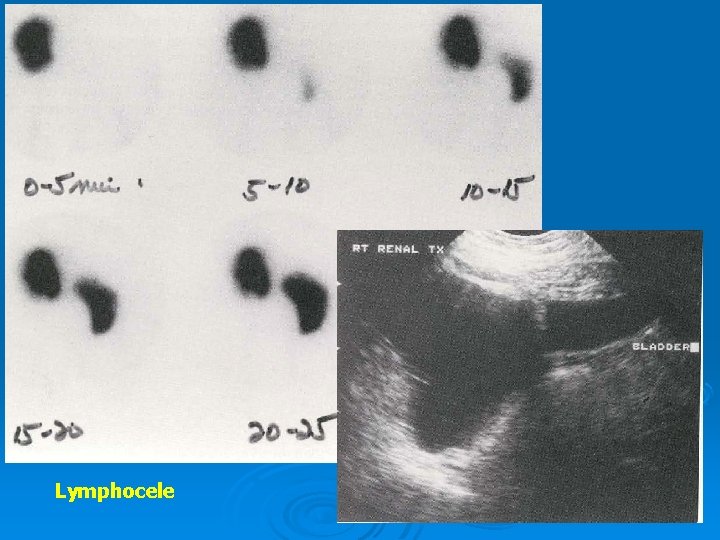

Surgical complications Ø US and Tc 99 m-MAG 3 images Ø Diuretic renography : Differentiate obstruction from simple pelvocalyceal dilatation

Lymphocele

Urinary Leak